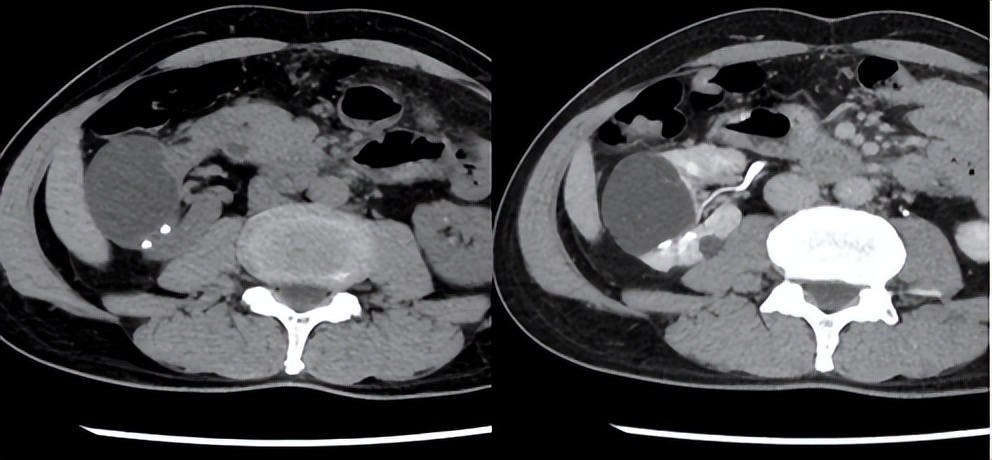

石不相瞒,相见恨晚。B超、CT、KUB+IVP、CTU的火眼金睛,令肾脏原形毕露,让结石无处遁形。结石成分分析、基因检测,揭开了结石的前世今生。结石不在沉默中爆发,就在沉默中灭亡。从体外震波碎石、开放手术取石到经皮肾镜、输尿管软镜碎石取石,肾斗士与肾结石的战争一直在路上。

肾盏头顶一片天(穹隆),脚踏一方土(结石)。肾盏的江湖地位一看身段二靠地段。

肾盏中重度积水或铸型结石负荷大,导致集合系统明显分离,宛若虎背熊腰的大家闺秀,广阔天地适合大手大脚。积水不明显的小肾盏,好比细胳膊瘦腿的小家碧玉,侧身天地只宜缩手缩脚。

倘若肾盏居于咽喉要地,生意兴隆通四海,财源茂盛达三江,可列为穿刺首选。要是肾盏位于穷乡僻壤,自古出山一条路,一片孤城万仞山,则作为专人专用定点清除刁民。

肾镜碎石,重在器尽其技、地尽其利、不拘一盏、不惜一战,总得深谋远虑、从长计议。石事求是、量肾订制、把盏言欢是确定穿刺肾盏的原则。盏各有志,不可小视。上盏:*瞻高**远瞩、得陇望蜀;中盏:左右逢源、委曲求全;下盏:下底传中、无问西东。

石不我予,咎由自取,山环水抱,取之有道。取道穿刺就是按图索骥、开天辟地。从11肋间到12肋下,不论是平行肾脏长轴还是垂直纵轴方向,肾斗士枕戈待旦,随时准备利剑出鞘,直插敌后(背侧肾盏)。